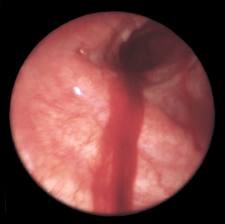

Инородное тело трахеи и бронхов

Инородные тела трахеи, бронхов – это чужеродные тела, которые попали в полость этих органов. Обычно они попадают в просвет гортани, бронхи, трахею по неосторожности, в результате проглатывания маленькими детьми. Также это возможно при рвоте, наличии зубных протезов, при привычке постоянно держать во рту различные предметы. Читать далее